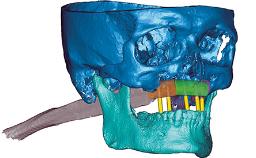

Rehabilitating an Edentulous Maxilla with Three Separate Bridges

A 55-year-old woman was referred to our clinic for implant therapy. She was healthy and had stopped smoking two years previously. Ten years before, the patient had received extensive dental treatment in both jaws. The patient reported that her dental condition had deteriorated progressively since that time. At the time of presentation, the maxillary bridge was loose. The clinical and radiographic examinations revealed a highly compromised situation for all the teeth that supported the bridge and for other teeth.